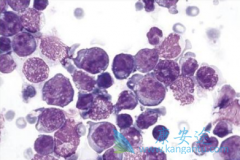

据海外医疗研究数据显示,多发性骨髓瘤是世界上发病率第二高的血液恶性肿瘤,每年都有数以万计新的骨髓瘤患者出现,在以往,我们用来治疗多发性骨髓瘤的抗癌靶向药物只要是沙利度胺,但是自从其导致许多新生儿出现了畸形后就被禁止生产了,如今我们用的 ...

多发性骨髓瘤是目前我国发病率增长最快的骨髓瘤疾病之一,很多人由于早期对自己身体的一些轻微的骨髓瘤症状不是很在意,导致患者的病情被拖入到了晚期,很多被检查出来是晚期多发性骨髓瘤的患者都失去了生活的希望,但是自从 来那度胺 这款专门用于治疗 ...